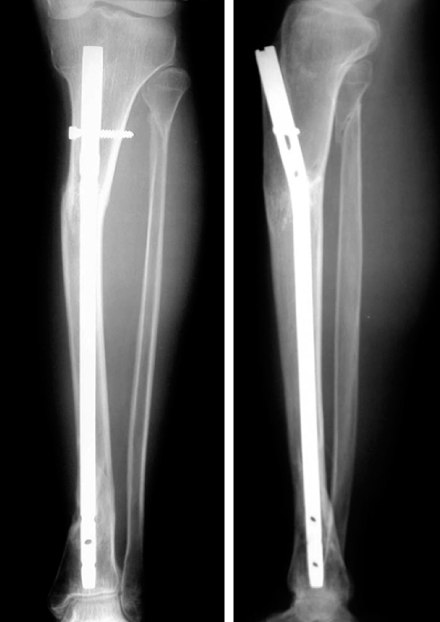

Fig. 6

Postoperative radiographs of this proximal tibial shaft fracture show good alignment after locked tibial nailing using the lateral starting point in line with the lateral intercondylar eminence and more proximal and posterior starting point.